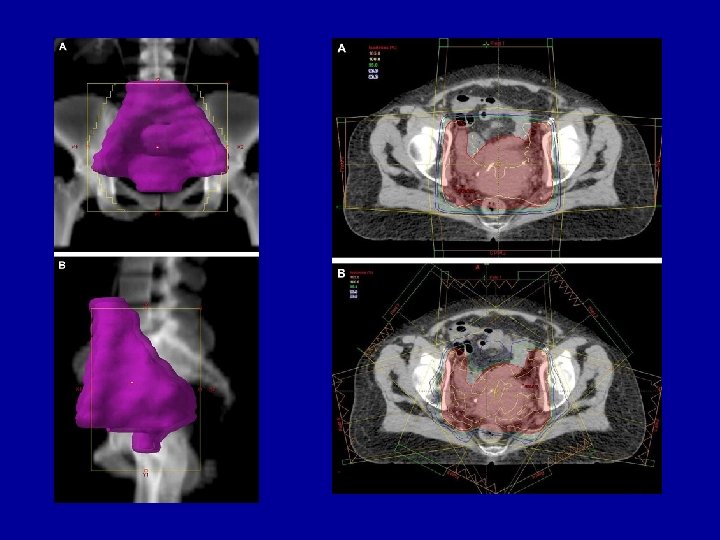

Conformal RT dose distributions

Conventional Target Volumes around a cancer (red). OAR 1 OTV = remainder of body GTV Gross tumour volume GTV CTV PTV OAR 2 CTV Clinical target volume contains normal tissue PTV Planning target volume contains normal tissue OAR = Organs at Risk – within CTV, PTV and OTV

Normal tissue volumes which have to be treated